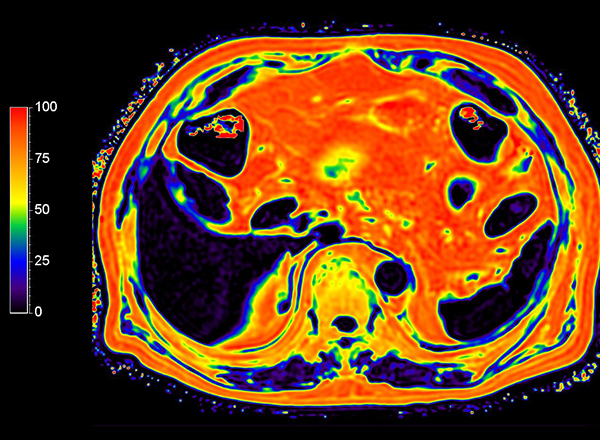

Axial mDIXON Quant